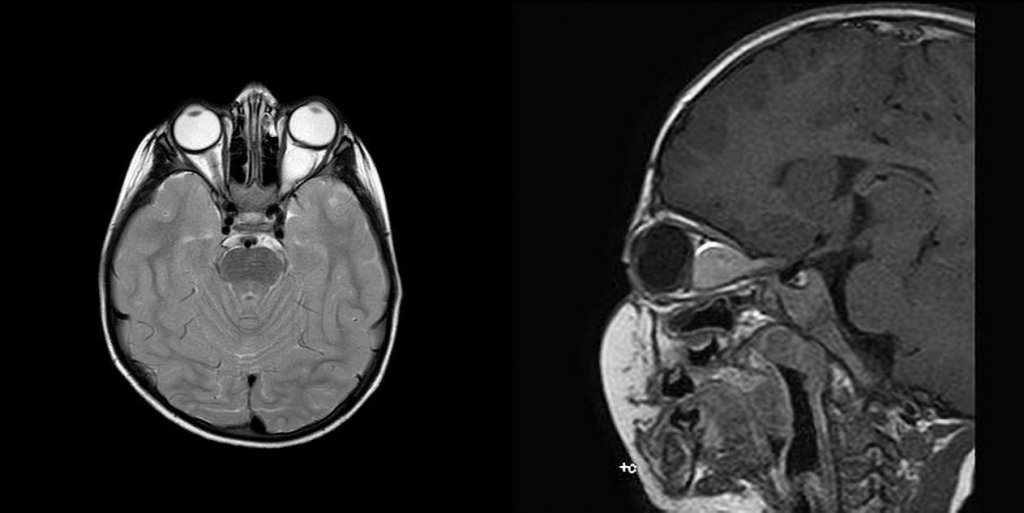

Гліома зорового нерву - пухлина, що виникає з гліальних клітин зорового нерву (див. на рис. МРТ знімки гліоми).

Гістологічно, більшість - пілоцитарні астроцитоми (WHO grade I). Може локалізуватись інтраорбітально та інтракраніально.

Окрім безпосереднього ураження зорового нерву, може поширюватись на хіазму (chiazma optica) та зорову радіацію (radiatia optica).Через таку локалізацію, діагностично важко відрізнити від гліом гіпоталамуса. В зв’язку з цим, в літературі зустрічаються такі варіації як гіпоталамічно-оптохіазматична гліома, або гліома зорового тракту, що не виключає ураження гіпоталамуса.

Радіографічно діагностують переважно інтракраніальні гліоми. В радіо-діагностиці інтраорбітальних немає необхідності.